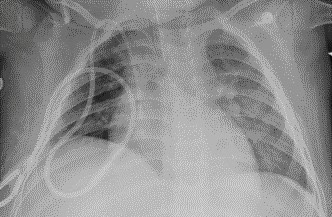

1915. Пациенту 5 лет с диагнозом «ювенильный миеломоноцитарный лейкоз» выполнена рентгенография грудной клетки в прямой проекции, рентгенологическая картина соответствует